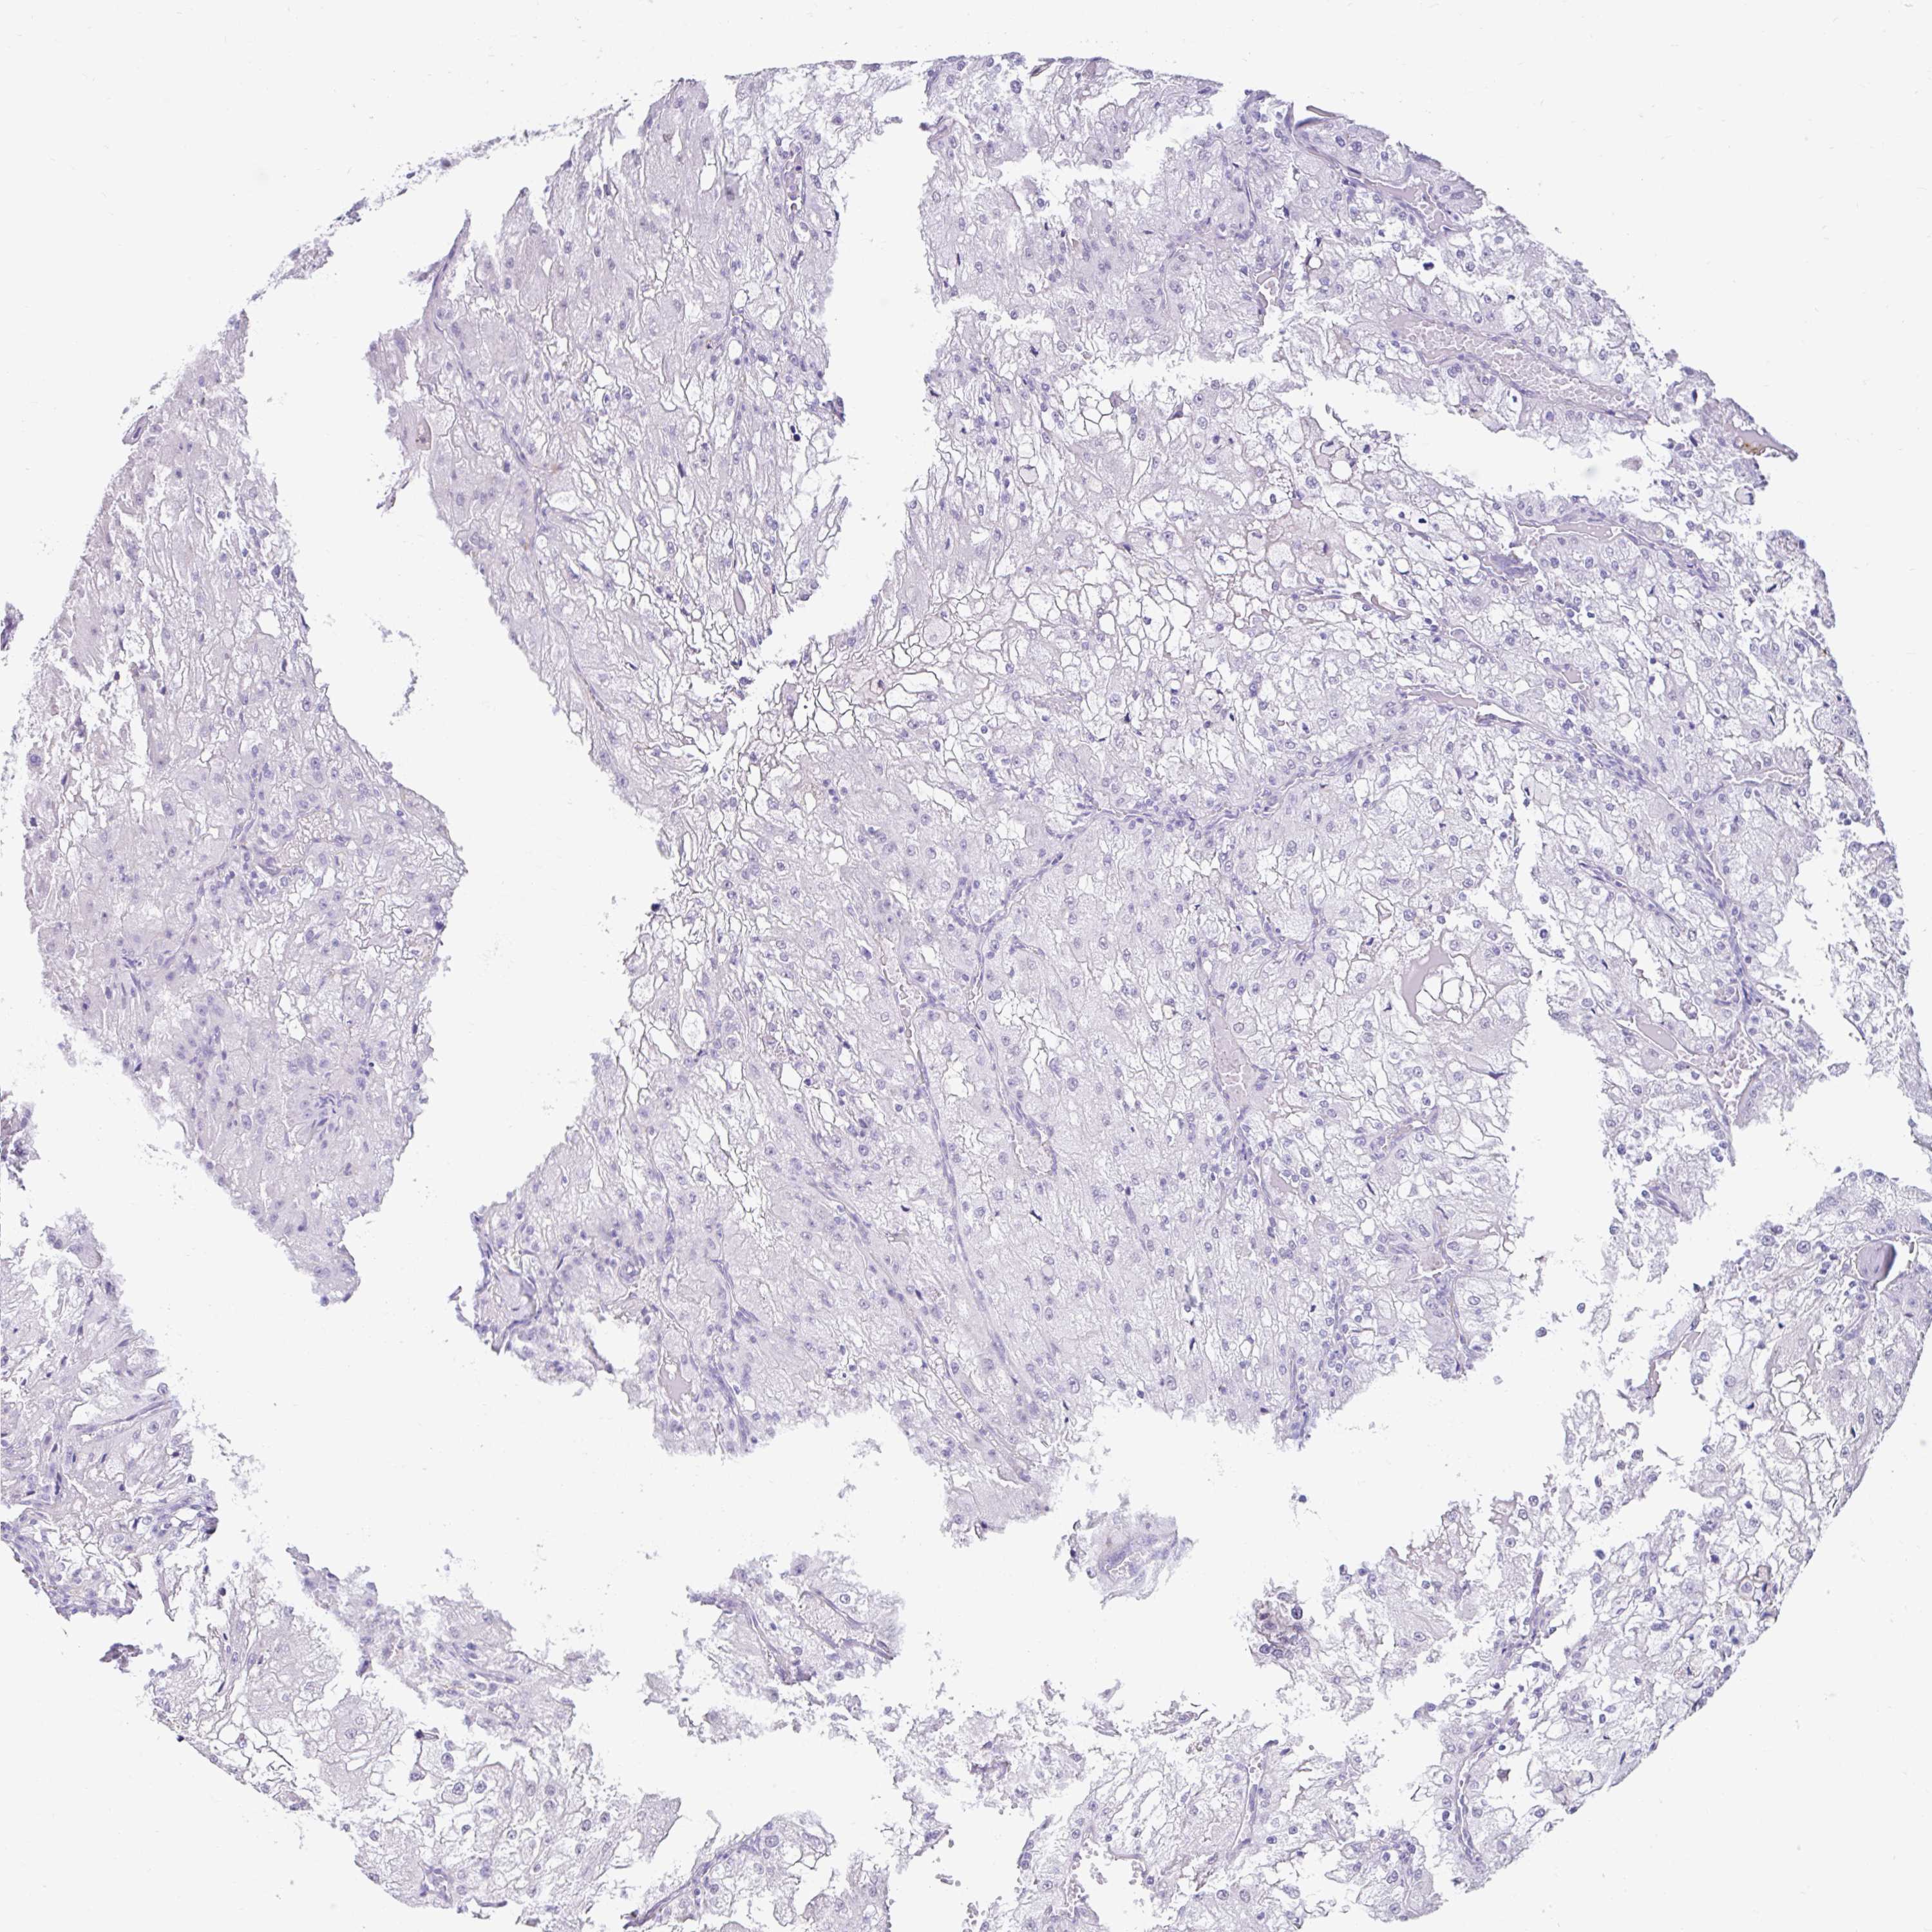

KIDNEY RENAL PAPILLARY CELL CARCINOMA (TCGA) - Interactive survival scatter ploti

The Survival Scatter plot shows the clinical status (i.e. dead or alive) for all individuals in the patient cohort, based on the same data that underlies the corresponding Kaplan-Meier plots. Patients that are alive at last time for follow-up are shown in blue and patients who have died during the study are shown in red.

The x-axis shows the expression levels (FPKM) of the investigated gene in the tumor tissue at the time of diagnosis. The y-axis shows the follow-up time after diagnosis (years). Both axes are complimented with kernel density curves demonstrating the data density over the axes. The top density plot shows the expression levels (FPKM) distribution among dead (red) and alive patients (blue). The right density plot shows the data density of the survived years of dead patients with high and low expression levels respectively, stratified using the cutoff indicated by the vertical dashed line through the Survival Scatter plot. This cutoff is automatically defined based on the FPKM cutoff that minimizes the p-score. The cutoff can be changed by dragging the vertical line or by entering a cutoff value in the square labeled "Current cut-off".

Under the Survival Scatter plot the p-score landscape (black curve; left axis) is shown together with dead median separation (red curve; right axis). Dead median separation is the difference in median mRNA expression between patients who have died with high and low expression, respectively. It is calculated as follows: median FPKM expression of dead patients with high expression - median FPKM expression of dead patients with low expression. This is intended to aid the user in visually exploring custom cutoffs and the associated p-scores and dead median separation.

Individual patient data is displayed and can be filtered by clicking on one or more of the category buttons on the top of the page. Categories describing expression level and patient information include: high, low, alive, dead, female, male and tumor stages. The scale of the x-axis can be toggled between linear and log-scale by clicking on the "x log" button. Mouse-over function shows TCGA ID, patient information and mRNA expression (FPKM) for each patient.

& Survival analysisi

Kaplan-Meier plots summarize results from analysis of correlation between mRNA expression level and patient survival. Patients were divided based on level of expression into one of the two groups "low" (under cut off) or "high" (over cut off). X-axis shows time for survival (years) and y-axis shows the probability of survival, where 1.0 corresponds to 100 percent.

DCAF17 is not prognostic in Kidney Renal Papillary Cell Carcinoma (TCGA)

Best expression cut offi

Based on the FPKM value of each gene, patients were classified into two groups and association between prognosis (survival) and gene expression (FPKM) was examined. The best expression cut-off refers the FPKM value that yields maximal difference with regard to survival between the two groups at the lowest log-rank P-value. Best expression cut-off was selected based on survival analysis .

When clicking on this number, the vertical dashed line indicating cut-off, the interactive survival plot, and the Kaplan-Meier curve will be adjusted to show results based on the best expression cut-off.

: 4.89